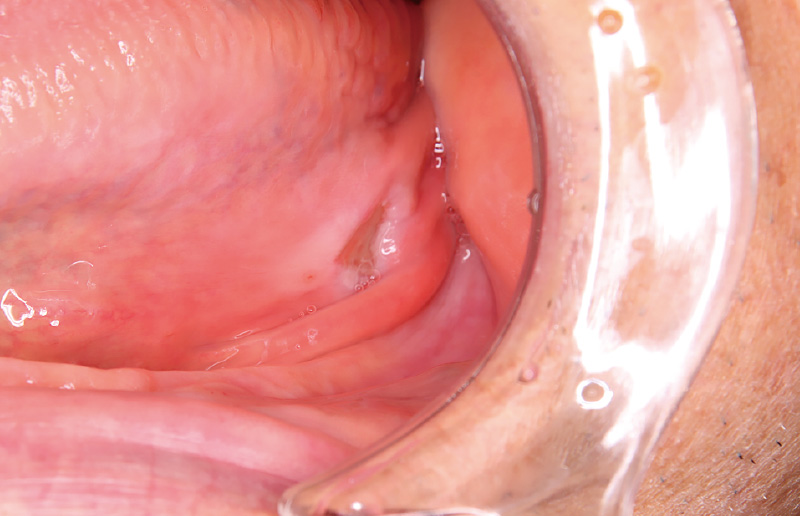

![[写真] 義歯不適合による褥瘡性潰瘍](/academic/dentalmagazine/wp-content/uploads/sites/2/2026/04//196-8_photo05.jpg)

図5 義歯不適合による褥瘡性潰瘍 -